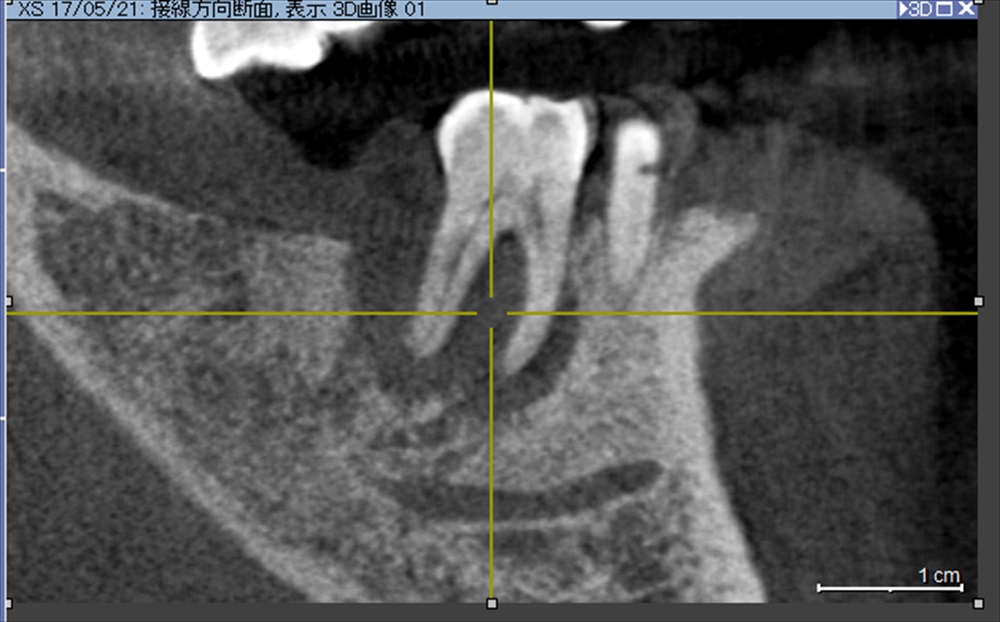

18年6月

明らかに歯の周りは再生した骨で埋まってきました。

揺れが消え痛みもなくなり

「魚を骨まで食べられる!」との事。